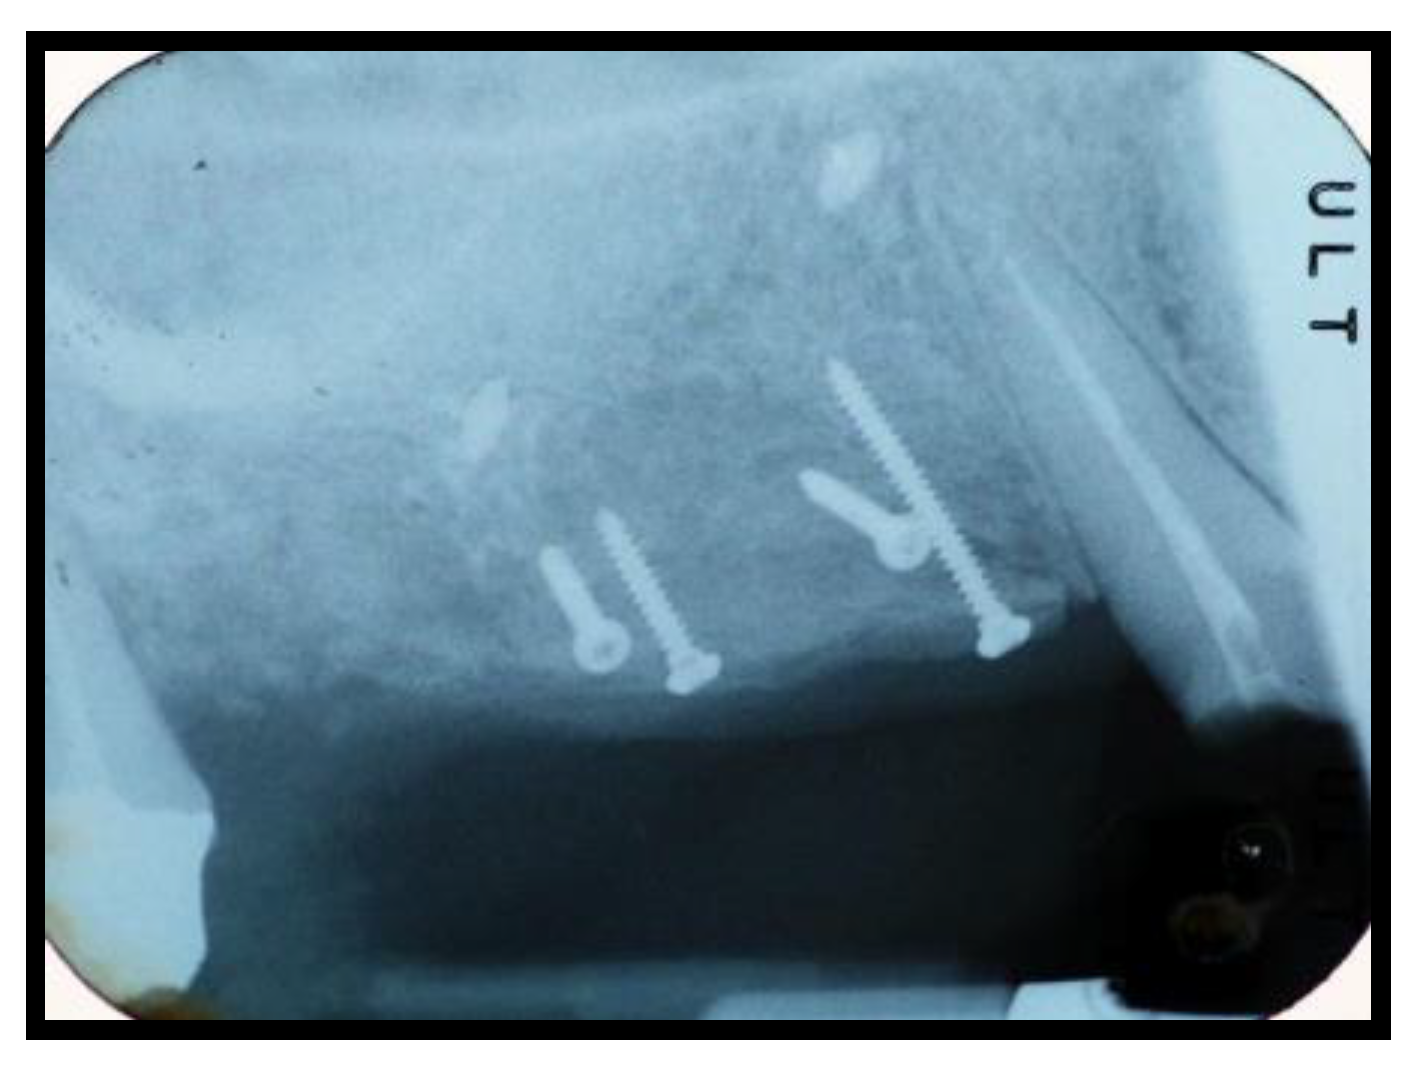

2.1. Surgical Procedures

2.2. Follow-Up